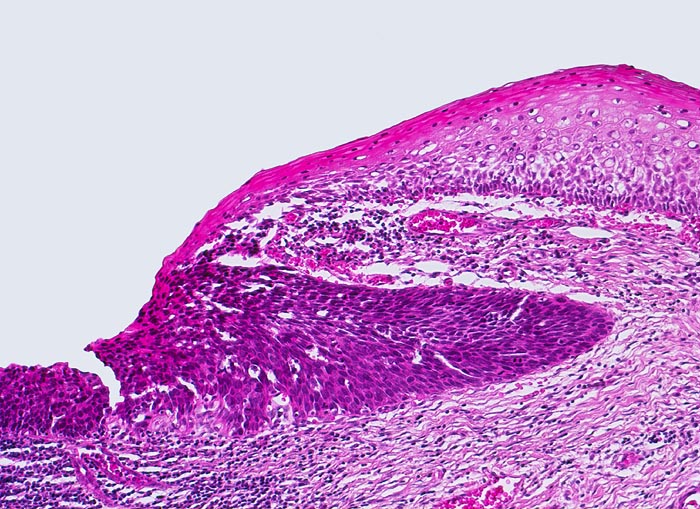

Das Carcinoma in situ wird in der Bethesda Klassifikation zusammen mit der mittelschweren und der schweren Dysplasie eingeteilt als high grade squamous intraepithelial lesion (HSIL). Im Vergleich zur schweren Dysplasie nehmen Grösse und Hyperchromasie der Kerne weiter zu. Die Zellgrösse entspricht dem Basalzelltyp. Das Chromatin ist grob verklumpt und unregelmässig verteilt. Der Kernhintergrund ist hell. Dadurch entsteht die an ein Leopardenfell erinnernde Kernstruktur. Grosse Nukleolen sind verdächtig auf eine bereits vorhandene Mikroinvasion (zweites Bildbeispiel). Zytologische und histologische Aufnahmen stammen von verschiedenen Patientinnen.